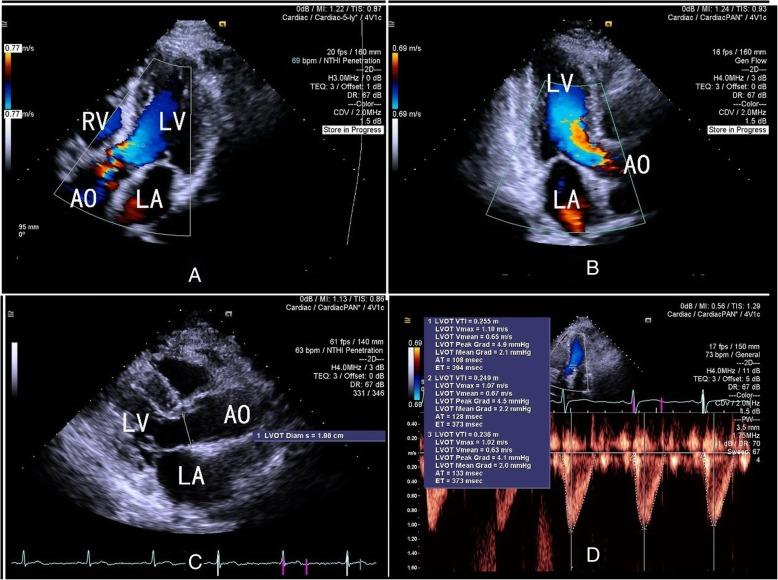

Three-dimensional color flow Doppler (3DCF) is a new convenient technique for cardiac output (CO) measurement. However, to date, no one has evaluated the accuracy of 3DCF echocardiography for CO measurement after cardiac surgery. Therefore, this single-center, prospective study was designed to evaluate the reliability of three-dimensional color flow and two-dimensional pulse wave Doppler (2D-PWD) transthoracic echocardiography for estimating cardiac output after cardiac surgery.

Post-cardiac surgical patients with a good acoustic window and a low dose or no dose of vasoactive drugs (norepinephrine < 0.05 μg/kg/min) were enrolled for CO estimation. Three different methods (third generation FloTrac/Vigileo™ [FT/V] system as the reference method, 3DCF, and 2D-PWD) were used to estimate CO before and after interventions (baseline, after volume expansion, and after a dobutamine test).

A total of 20 patients were enrolled in this study, and 59 pairs of CO measurements were collected (one pair was not included because of increasing drainage after the dobutamine test). Pearson's coefficients were 0.260 between the CO-FT/V and CO-PWD measurements and 0.729 between the CO-FT/V and CO-3DCF measurements. Bland-Altman analysis showed the bias between the absolute values of CO-FT/V and CO-PWD measurements was - 0.6 L/min with limits of agreement between - 3.3 L/min and 2.2 L/min, with a percentage error (PE) of 61.3%. The bias between CO-FT/V and CO-3DCF was - 0.14 L/min with limits of agreement between - 1.42 L /min and 1.14 L/min, with a PE of 29.9%. Four-quadrant plot analysis showed the concordance rate between ΔCO-PWD and ΔCO-3FT/V was 93.3%.

In a comparison with the FT/V system, 3DCF transthoracic echocardiography could accurately estimate CO in post-cardiac surgical patients, and the two methods could be considered interchangeable. Although 2D-PWD echocardiography was not as accurate as the 3D technique, its ability to track directional changes was reliable.